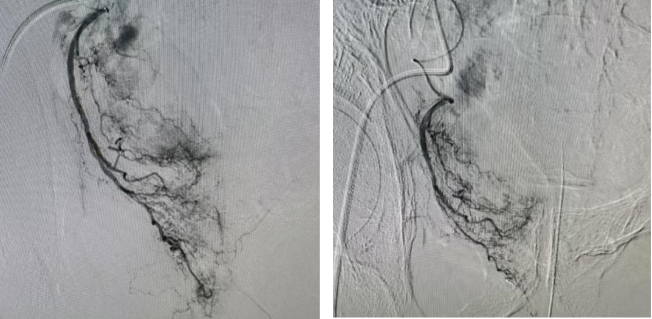

手术当日,手术团队在先进的影像设备引导下,精准地将栓塞材料送达右侧膀胱动脉的特定部位,成功阻断绝大部分膀胱恶性肿瘤血液供应,达到了预期的治疗效果。手术过程顺利,患者术后24小时即可下床活动。目前该患者恢复良好,血尿量明显减少,血尿颜色明显变淡,且未出现严重并发症。

栓塞前肿瘤血供明显 栓塞后肿瘤血供明显减少